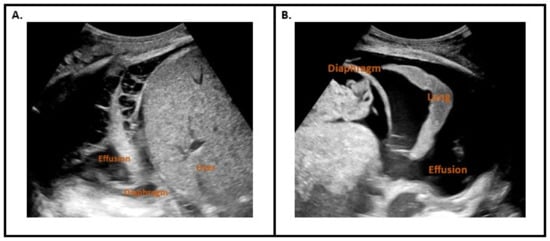

| Thoracic Ultrasound | High risk findings: Homogenous echogenicity Hyperechoic septation Thickened parietal pleura |